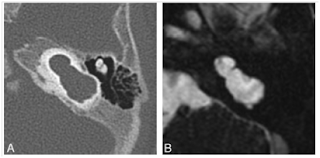

Şekil 1: Michel Labirent aplazisi. Aksiyel (A) ve koronal (B) kesitlerde normal iç kulak yapıları bulunmamaktadır. İyi gelişmiş bir iç kulak kanalının olmayışı, tabloyu labirentitis ossifikans olgusundan ayırmaktadır.

Bu sınıflamada Michel aplazisi "Total Kohlea ve Vestibül Aplazisi" olarak tanımlanır (Şekil 1). Gebeliğin 3-4.haftalarındaki etkilenmeler vestibül vardır ve "Kohlear Aplazi" olarak tanımlanmıştır (Şekil 3).

Labirentin tam ossifikasyonu durumunda klinik tablonun labirent aplazisinden ayrılabilmesi için, iç kulak yapılarının boyutları ve İAK anatomik yapısı önemlidir.50